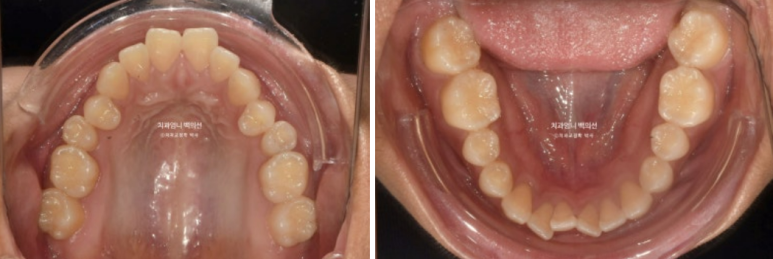

23.11

23년 11월 개방교합 치료를 위해 내원한 환자분입니다.

삐뚤한 치아 배열은 사랑니 공간을 이용해서 어금니를 뒤로 밀어내어 해결하기로 하고 앞니 개방교합은 어금니 함입을 통해 해결하기로 합니다.

악궁확장에 대해서는 악궁이 좁은 게 아니라 단순히 첫번째 작은어금니가 입천장으로 기울어진 상황이라 악궁확장은 따로 하지 않습니다.